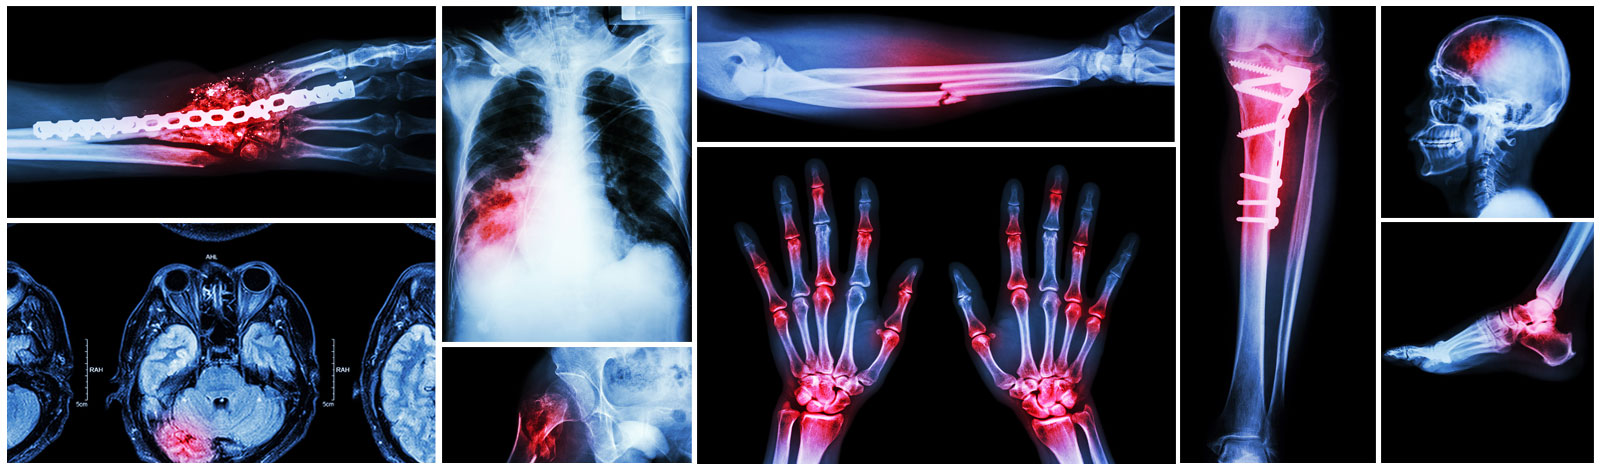

Trauma

We provide services for some of the most complex orthopaedic injuries throughout the region. Our Orthopaedic Trauma Surgery Clinic offers numerous services including fracture care, associated soft tissue injuries, skeletal realignments and stabilizations using closed and surgical techniques.

We deal in both conservative and operative management of almost all major and minor fractures both in adults and children .

We undertake all major surgeries like Closed interlocking nailing Plating of all major bones MInimally invasive plate j.

Treatment of hip fracture in old people including Closed reduction and pinning for neck femur fracture Proximal femoral nail for IT fracture Hemiarthoplasty in neck fracture .

Treatment of paediatric trauma Closed and open reduction of supra condylar fracture Flexible nailing for femur fracture Lateral condyle fracture Epiphysisal injury.